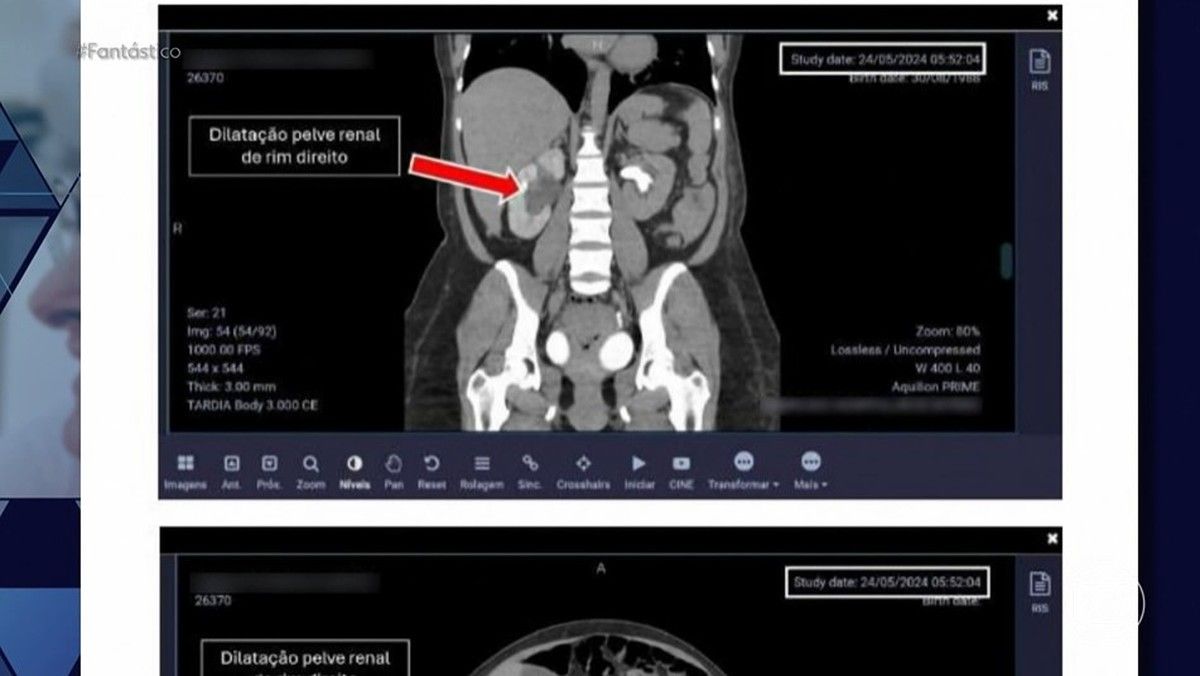

Médica obstetra tem registro suspenso por denúncias no Rio de Janeiro. Reprodução: Globo

Mulheres que vivenciaram partos sob a responsabilidade da médica influencer Anna Beatriz Herief, mais conhecida como Bia Herief, têm compartilhado histórias alarmantes sobre violência obstétrica. Essas denúncias, que recententemente ganharam força, culminaram na suspensão do registro profissional da médica pelo Conselho Regional de Medicina do Rio de Janeiro no início de abril de 2025.